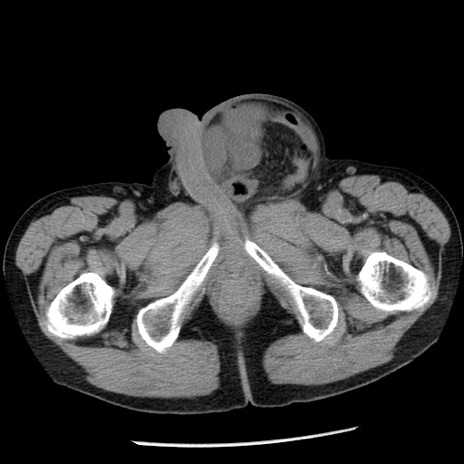

冠状断像